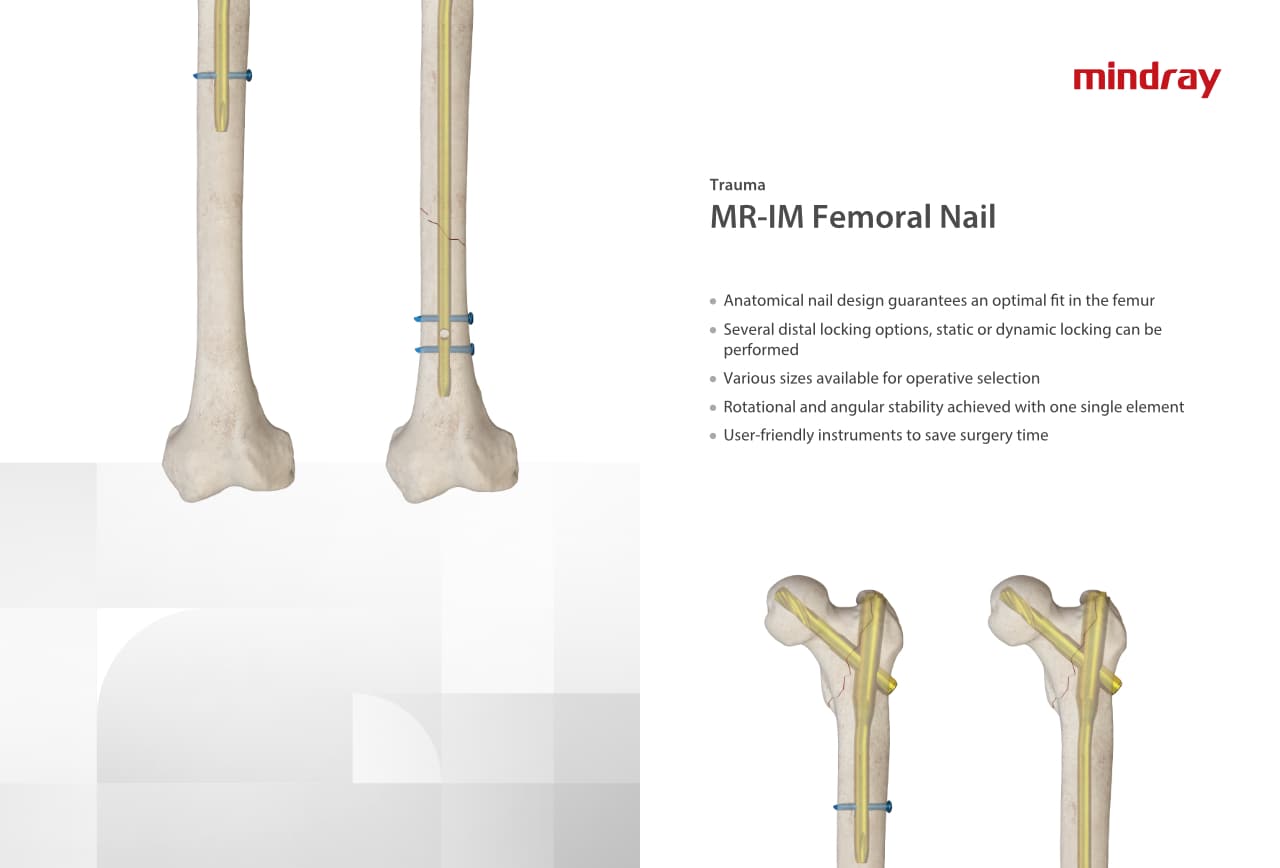

Trauma